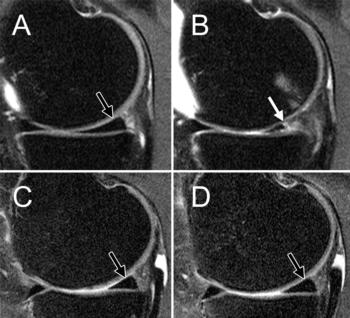

Figure 1. Baseline and follow-up MRIs of the right knee of two obese women, one who lost no weight (A, B), and one who lost weight (C, D).

Cartilage degeneration was significantly lower in the weight loss group, compared to the control group over the 96 months. However, this finding was only present among the patients who lost weight through diet and exercise or diet alone. Although patients who only exercised lost as much weight as patients who dieted alone or dieted and exercised, weight loss through exercise alone showed no significant difference in cartilage degeneration, compared to the group who lost no weight.